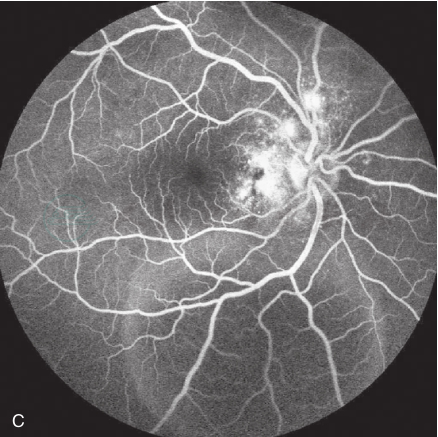

图2 交感性眼炎引起渗出性视网膜脱离

A.患者女,32岁,右眼视力下降3年,加重一个月,视乳头充血,眼底偏红,色素不均,中心凹反光消失;B.左眼外伤后10年,视乳头充血,晚霞状眼底;C.右眼视乳头旁多灶性强荧光,部分融合呈片状,下方可见葫芦状强荧光,视网膜浅脱离;D.外伤眼视乳头周围视网膜色素上皮及脉络膜弥散性萎缩,黄斑中心局部高荧光,晚期无扩大,考虑为窗样缺损;E.OCT检查,右眼玻璃体内渗出物,黄斑中心凹脱离及周边视网膜浅层脱离;F.外伤眼可见黄斑中心凹萎缩,无渗出表现(易长贤提供)

急性期造影的静脉早期,在RPE和脉络膜水平出现多发性强荧光渗漏点,在后期这些强荧光点可融合成片状强荧光,炎症严重的患者可形成多囊状或葫芦状改变(图2B、C)。另外一个常见的表现是视乳头渗漏荧光、黄斑水肿和渗出性视网膜脱离。在一些患者可出视网膜血管荧光素渗漏、血管壁染色等改变。在疾病的慢性期或反复发作的葡萄膜炎患者,可出现造影早期多发性弱荧光区,后期染色,此种荧光改变的部位与临床上所见的Dalen-Fuchs结节的分布相一致。在慢性期,这些结节所在的部位萎缩,造影时呈窗样缺损。